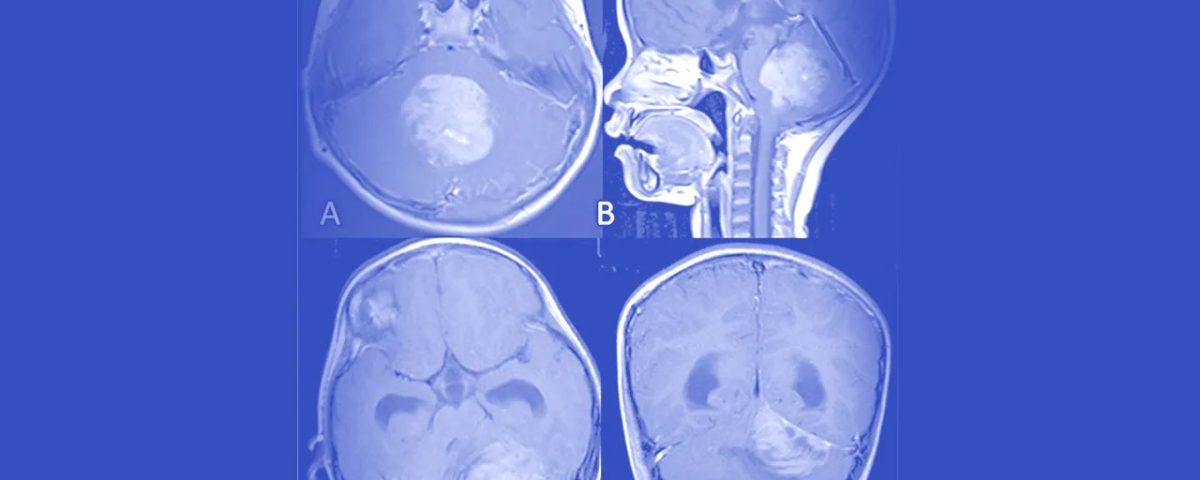

۲. آزمایشهای تصویربرداری: تصویربرداری رزونانس مغناطیسی (MRI) و اسکن توموگرافی کامپیوتری (CT) برای ایجاد تصاویر دقیق از مغز و مکانیابی هرگونه تومور استفاده میشوند.

۳. بیوپسی یا برداشتن با جراحی (Biopsy): در بیشتر موارد، یک نمونه بافت در حین جراحی برای برداشتن تومور گرفته میشود. سپس یک آسیبشناس سلولها را زیر میکروسکوپ بررسی میکند تا تشخیص مدولوبلاستوما را تأیید کند. بیوپسی معمولاً تنها در صورتی انجام میشود که تستهای تصویربرداری قطعی نباشند.